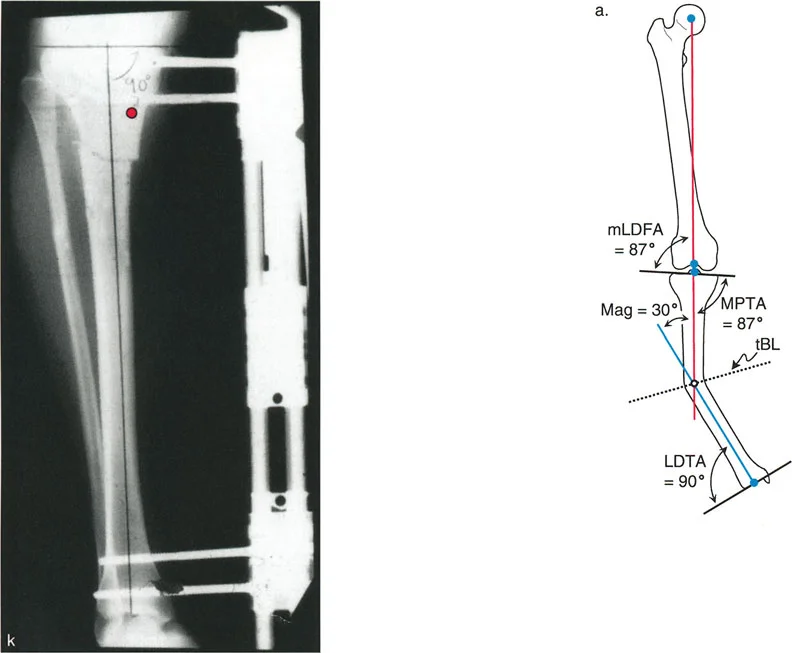

التصوير بالأشعة السينية (X-rays):

- أشعة الساق الكاملة الواقفة (Full-length Standing X-rays): هذه هي الأداة التشخيصية الأكثر أهمية لتشوهات الأطراف. يتم أخذ الصورة بينما يقف المريض، مما يسمح بتقييم المحور الميكانيكي للطرف بأكمله (من الورك إلى الكاحل) تحت تأثير تحمل الوزن. تتيح هذه الصور للجراح قياس زوايا محددة بدقة وتحديد "مركز دوران التشوه" (CORA) – وهو النقطة المحورية التي يجب أن يتم التصحيح حولها.

التصوير المقطعي المحوسب (CT Scan):

- يُستخدم التصوير المقطعي المحوسب لتقييم التشوهات الدورانية بشكل خاص، وللحصول على صور ثلاثية الأبعاد للعظام، مما يساعد في التخطيط الجراحي المعقد.

إن نجاح جراحة تصحيح تشوهات الأطراف يعتمد بشكل كبير على التخطيط المسبق الدقيق. هذا التخطيط أشبه برسم خارطة طريق هندسية تضمن أن كل خطوة جراحية تقود إلى النتيجة المرجوة. يعتمد هذا التخطيط على "مبادئ بالي" التي تحدد ثلاثة متغيرات هندسية أساسية في كل حالة:

- مركز دوران التشوه (CORA - Center of Rotation of Angulation): هذه هي النقطة المحورية للتشوه في العظم. يحددها الجراح من خلال رسم محاور الطرف قبل الجراحة.

- محور تصحيح الزاوية (ACA - Angulation Correction Axis): هذه هي النقطة التي يدور حولها الجزء البعيد من العظم لتصحيح التشوه. يتحكم الجراح في هذه النقطة عن طريق وضع المفصلات على المثبت الخارجي أو نقطة الارتكاز للوحة التثبيت.

- مستوى قطع العظم (Osteotomy Level): هذا هو الموقع الفعلي الذي يتم فيه قطع العظم. يتحكم الجراح بشكل كامل في هذا المتغير، ويتم اختياره بناءً على عوامل مثل الأنسجة الرخوة، وجودة العظم، ونوع الأجهزة المستخدمة.

النتيجة النهائية للتصحيح تعتمد كليًا على كيفية ارتباط هذه المتغيرات الثلاثة ببعضها البعض. الفشل في التخطيط الدقيق يمكن أن يؤدي إلى "تشوهات ثانوية" غير مرغوب فيها، مثل انحراف المحور الميكانيكي أو ترجمة (إزاحة) العظم.